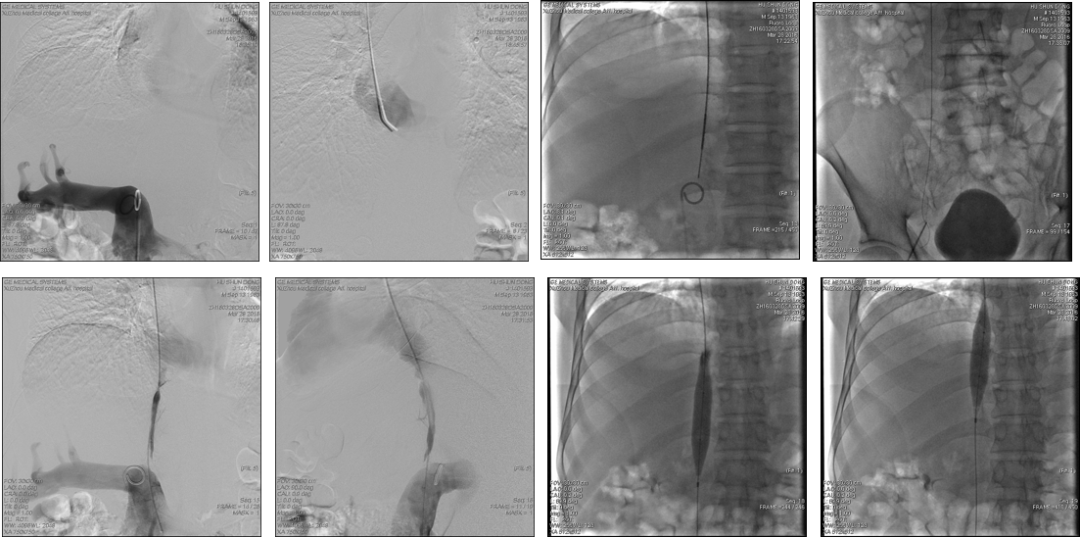

右颈静脉与肝左、中静脉闭塞

肝静脉广泛性阻塞介入治疗-- TIPS

女,27岁,腹胀腹水3月,三支肝静脉闭塞,无副肝静脉和尾状叶交通静脉,尾状叶增大致左右门脉分支汇合处向前移位,经下腔静脉直接穿刺门脉需要经过较长段的肝实质。

创新--敢为人先

★ 疑难之处:下腔静脉阻塞端危险交通支

难在透视下看不到血管,破膜(开通)穿刺针进入交通之后将导致血管破裂和出血

★ 疑难病例:下腔静脉长节段阻塞

★ 疑难病例:下腔静脉全程闭塞

男性,54岁,胸腹壁静脉曲张20余年